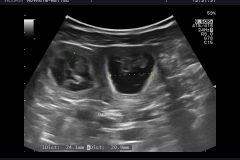

​Am Freitag den 15.10.2021 um 4.01 Uhr ging es los und Talulah unser Wirbelwind , hatte es wie immer eilig, den in nur 130 Minuten waren alle sechs Welpen auf der Welt, Drei stramme Buben mit einem Gewicht von  325, 324 und 343 Gramm und drei Mädels mit 321, 259 und 226 Gramm. Alle waren gleich munter und auf dem Weg zur Milchbar. Um 6.15 nachdem der letzte Welpe geboren war, warteten wir trotzdem noch drei Stunden den laut Ultraschall wurden ja mehr Welpen gesehen.